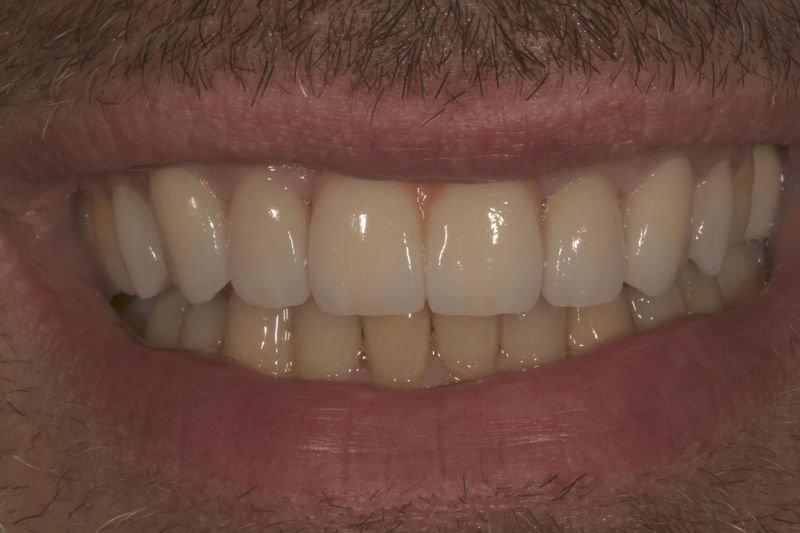

Amplia gama de tratamientos para mejorar la apariencia de la sonrisa, corrigiendo el color, la forma, el tamaño, la alineación y la posición de los dientes. Los procedimientos más comunes y solicitados incluyen el blanqueamiento dental, las carillas y coronas, así como las resinas.

Son restauraciones que cubren toda la cara frontal del diente, generalmente empleadas en el sector anterior y cuya finalidad es primariamente estética.

Restauraciones fabricadas en el laboratorio con materiales estéticos, los cuales cubren de manera total dientes anteriores y posteriores. Se utilizan primariamente para restaurar dientes con caries, fracturas y/o defectos amplios, así como soportes de puentes. Para poder enviar el caso al laboratorio se toman impresiones utilizando materiales de impresión o técnicas modernas digitales.